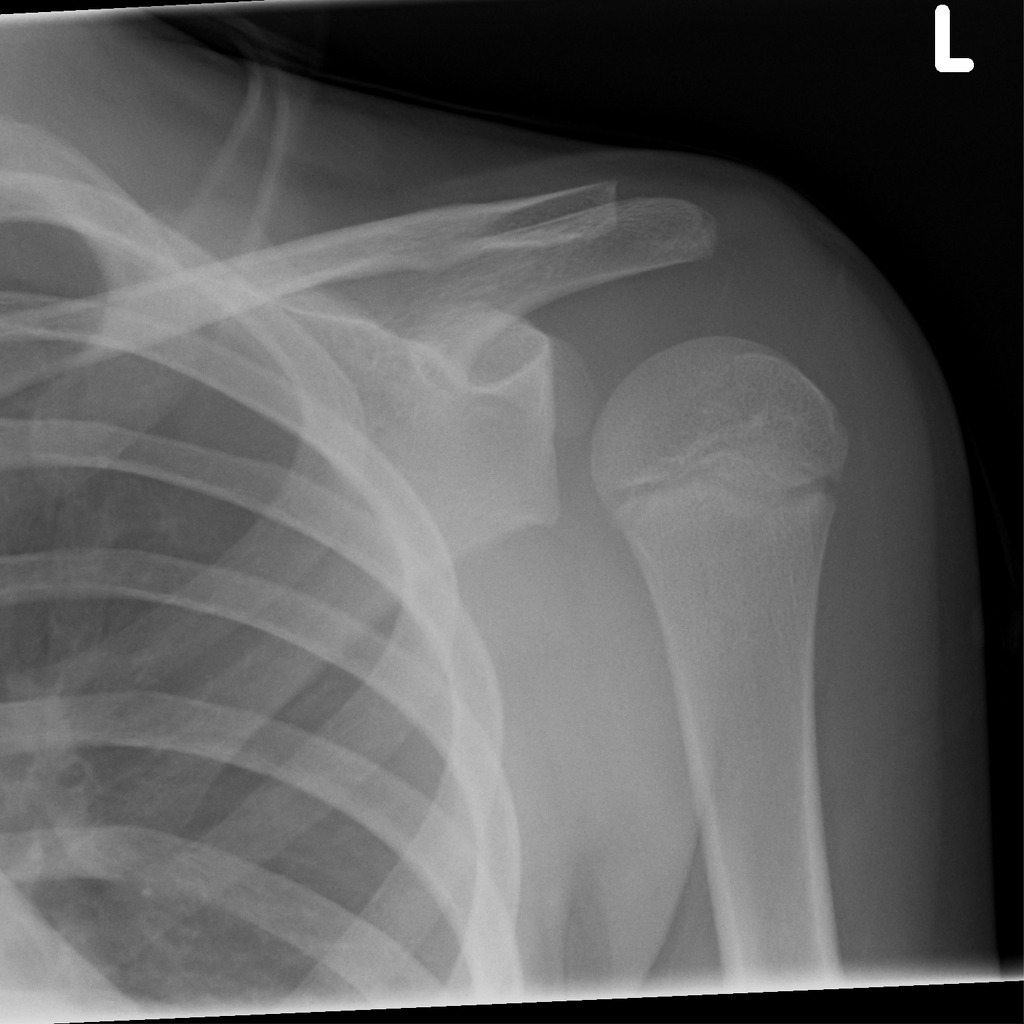

What injury is this? What are the radiographic features?

Posterior shoulder dislocation

What can cause posterior shoulder dislocations?

What must you check for in posterior shoulder dislocations?

Bilateral dislocations

Why can posterior dislocations be missed initially on frontal radiographs in 50% of cases?

as the humeral head appears to be almost normally aligned with the glenoid

Which view is preferred for diagnosis of posterior shoulder dislocations?

Axillary view